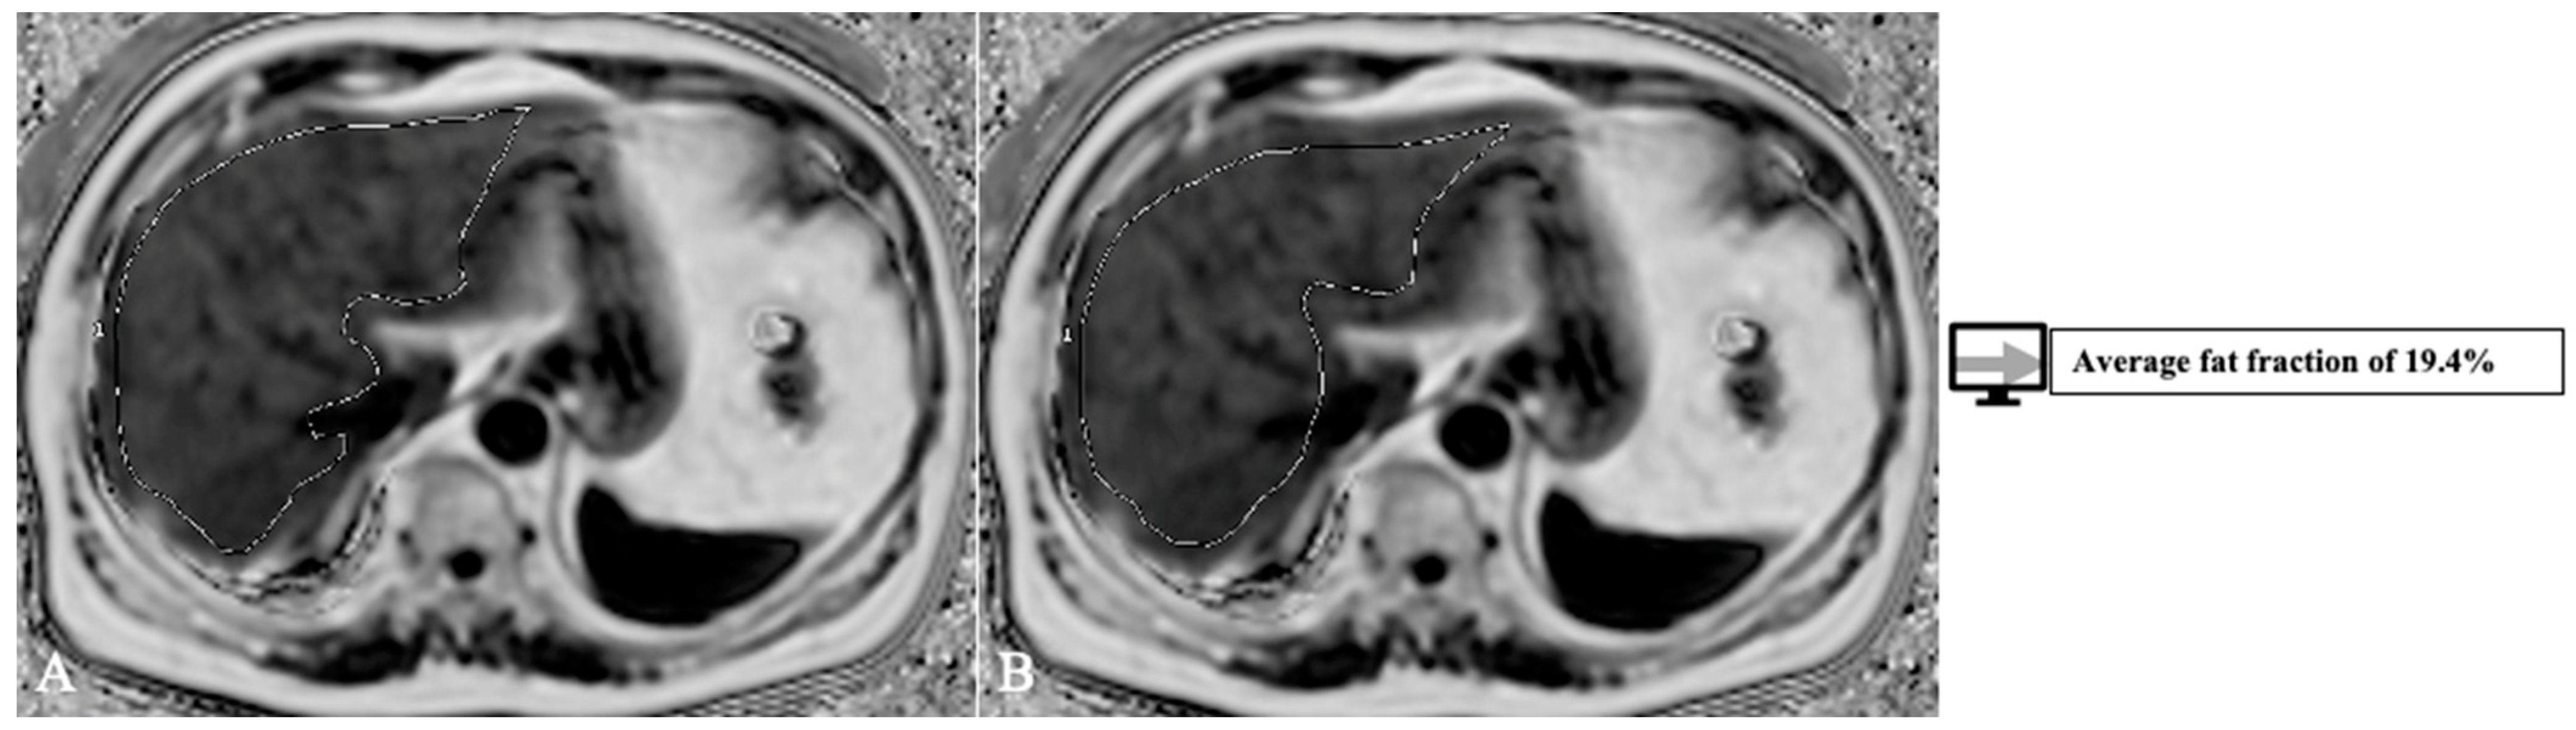

- Gu, J.; Liu, S.; Du, S.; Zhang, Q.; Xiao, J.; Dong, Q.; Xin, Y. Diagnostic value of MRI-PDFF for hepatic steatosis in patients with non-alcoholic fatty liver disease: a meta-analysis. European radiology 2019, 29, 3564–3573. [Google Scholar] [CrossRef]

- Jimenez-Pastor, A.; Alberich-Bayarri, A.; Lopez-Gonzalez, R.; Marti-Aguado, D.; França, M.; Bachmann RS, M.; Marti-Bonmati, L. Precise whole liver automatic segmentation and quantification of PDFF and R2* on MR images. European radiology 2021, 31, 7876–7887. [Google Scholar] [CrossRef]

| Jimenez-Pastor et al. [69] | 2021 | Liver segmentation, fat and iron quantification | MRI | DL | 93% |